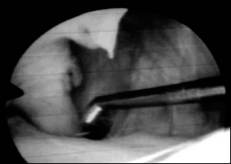

» CIRUGÍA ARTROSCÓPICA

» Rodilla:

• Osteocondritis disecante

• Sustitución de ligamento cruzado

• Limpieza articular

• Meniscos

» Codo:

• Fragmentación apófisis

coronoides

• No unión proceso ancóneo

• Osteocondritis

» Cadera:

• Rotura de ligamento redondo

• Forage